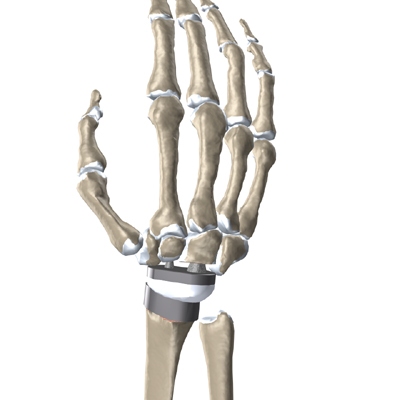

The hand bones and the radius bone of the forearm are then prepared with special rasps. The rasps are used to:

Bore Holes

in the bone for the metal stems of the:

Replacement Joint

The surgeon will take some time to get the stems to fit tightly. The joint is put in place and tested through its range of motion to make sure it moves correctly. Once the surgeon is satisfied with the fit, the stems of each metal implant are:

Cemented into Place